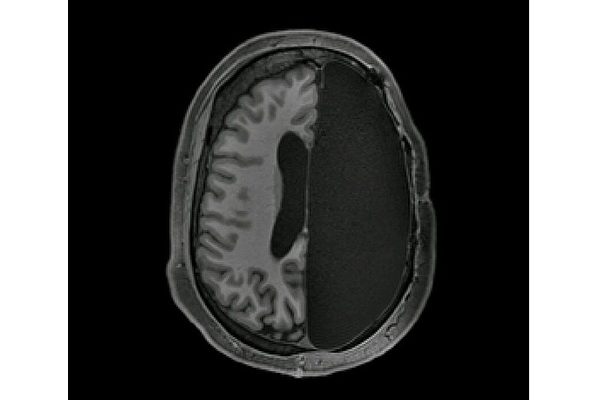

研究人员让他们放松地躺在功能磁共振成像(fMRI)机器内,但保持不要睡着的状态,记录他们在放松状态下,脑部控制视觉、运动、情感和认知的各个区域自发的信号活动,将数据与1500个正常工作大脑的神经信号进行对比。

研究者原以为,只靠半个大脑工作的脑神经网络之间的联系,将比完整大脑神经网络之间的联系弱得多。但是他们吃惊地发现,半个大脑总体的神经联系模式完全正常,而不同的神经网络之间的联系比完整大脑更强。

主要研究者加州理工学院的克莱曼(Dorit Kliemann)说:“靠半个大脑工作的研究志愿者有完好的语言技能,在他们接受扫描的时候,我们简单寒暄了几句,他们和我扫描过的上千人没有不同。当我坐在电脑屏幕前面,看着扫描影像上出现的半个大脑的时候,我不禁惊叹这真的是刚才我见到的研究志愿者吗?”